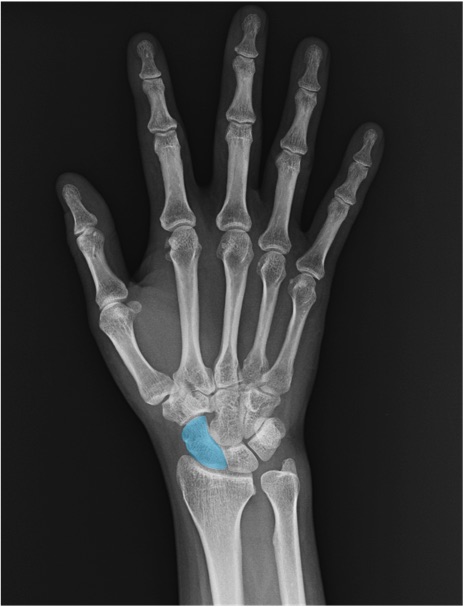

舟状骨(scaphoid)の手関節レントゲン画像における正常解剖

月状骨(lunate)